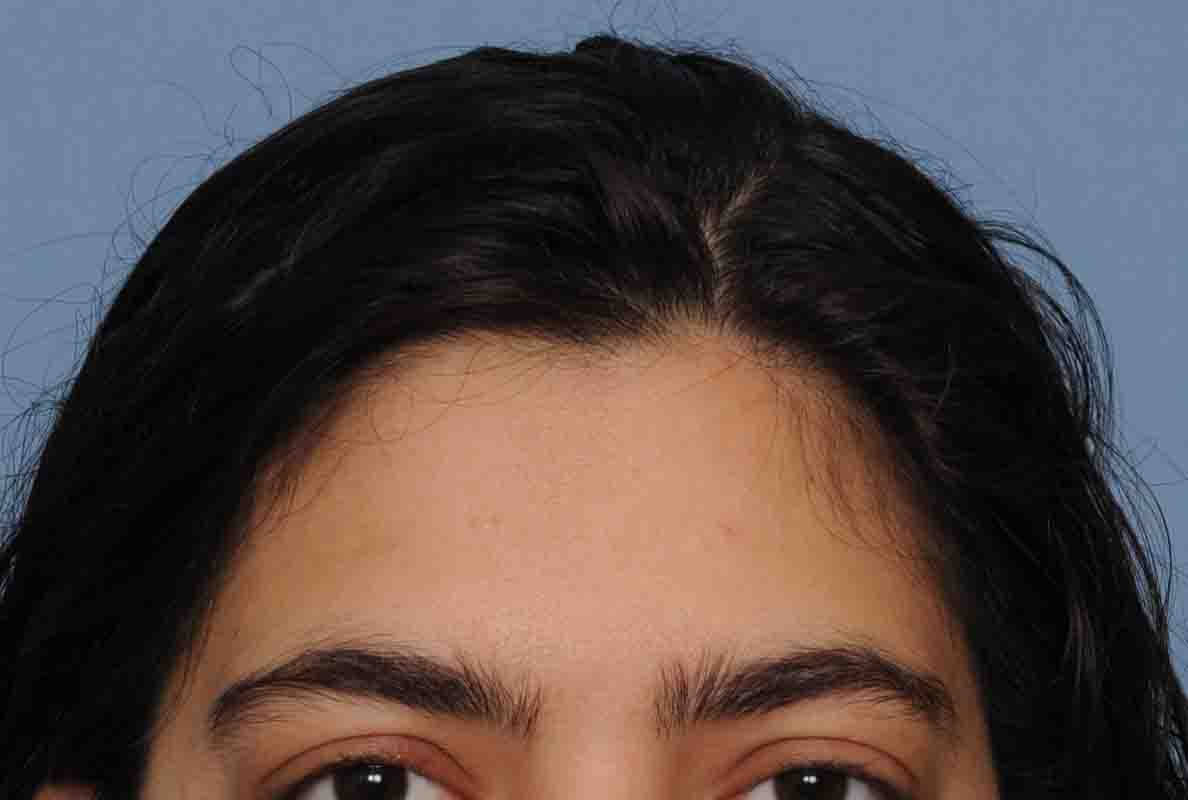

Patient 123

Desire for additional skull augmentation after a prior PMMA bone cement placement on the back of her head.

Placement of a custom skull implant to supplement her prior bone cement augmentation for an overall greater skull enhancement effect.